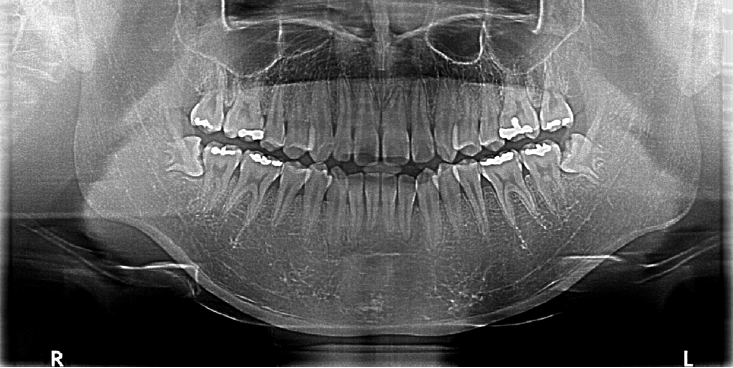

Figure 1.

Preoperative panoramic radiograph showing bilaterally impacted mandibular third molars without apparent bony pathology.

Intraoral examination revealed no significant abnormalities. Panoramic radiography showed impacted mandibular third molars (#38 and #48) bilaterally as shown in (Fig. 1).